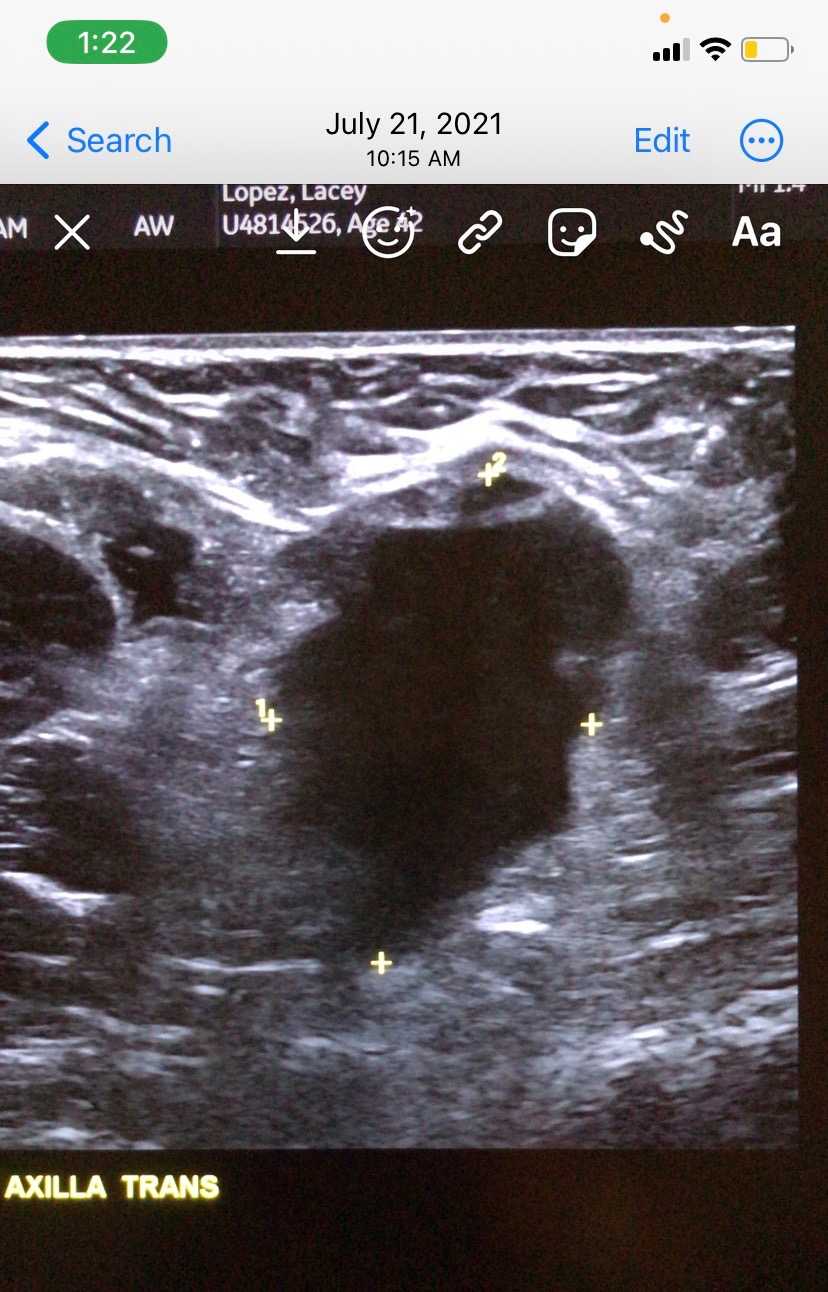

For some background, Lacey was first diagnosed November of 2018, with a 2nd diagnosis July 2021. She underwent two surgeries in March 2019 and April 2019 and all of the cancer was removed.

Her 2nd diagnosis came shortly after she miscarried twins in July 2021, she found out breast cancer came back & metastasized in her armpit and near her clavicle. Due to the horrible side effects of the first chemo treatment at a high dose, it was recommended she would be treated with 26 rounds of low dose chemo in 2022, which resulted in 5 benign tumors & 5 malignant tumors in her liver (which were miraculously healed - another story to tell sometime later).

(Above picture: Tumor scan of armpit July 2021)